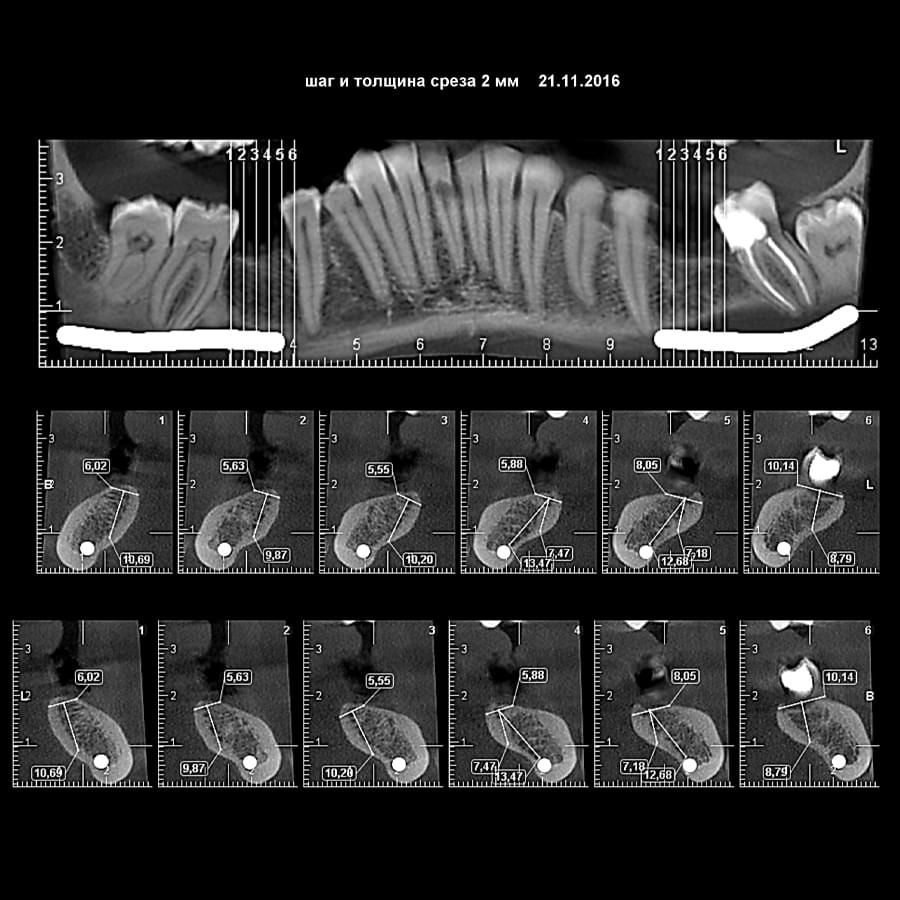

Головний недолік 2D-рентгену — це площинне зображення. Зуби, корені, щільна кістка та гайморові пазухи накладаються один на одного, створюючи «візуальний шум».

Візуальне порівняння (Кейс одного пацієнта)

Зуб — це не просто монолітний об'єкт, а складна система мікроканалів. На плоскому 2D-знімку вони часто перекривають один одного, створюючи ілюзію простої анатомії.

При плануванні імплантації лікарю важливо знати дві речі: об'єм кістки та точне розташування нервів.

КТ дозволяє провести віртуальну операцію: встановити імплант у програмі, виключивши будь-які ризики травмування пацієнта.